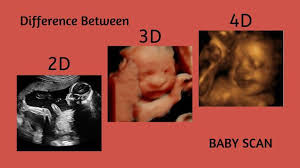

The terms 2d 3d and 4d stand for two dimensional three dimensional and four dimensional respectively. So what is the difference between 3d printing and 4d printing. However in most cases 2d ultrasound is carried and images from 3d and 4d are used in conjunction to arrive at conclusions. For example in a 4d movie of the avengers you might feel a static electricity in the air causing hair to stand up when thor summons lightening.

The main difference is that 3d focuses on the visual effects whereas 4d adds a tangible or tactile aspect to your movie experience. In 4d 3 4 images are taken per second which gives you an illusion of a movie. Or drops of water land on you when iron man flies by the bay. Difference between 3d and 4d images the four dimensional cube tesseract is one example of how the three dimensional world described by x y and z can extend into a fourth one.

3d and 4d ultrasound. A car has three dimensions. A 4d movie is a 3d movie with additional effects providing a real life experience emitted in special cinemas. 3d images are used to show you three dimensional external images that may be helpful in diagnosing issues such as a cleft lip.